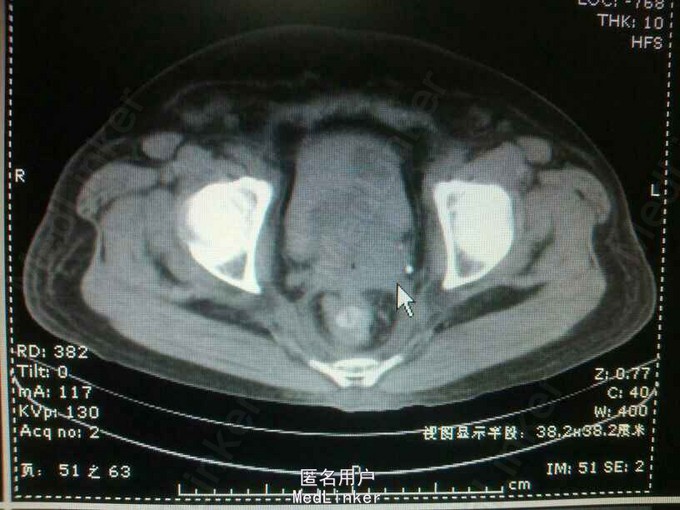

55岁,女性,宫颈癌放疗后两年,阴道出血半年,少尿20天

双肾区叩痛(+-),耻骨上区皮肤增厚,无明显压痛!会阴及双下肢水肿明显! 辅助检查:ct:双肾轻度积水,双侧输尿管全程扩张。膀胱充盈,伴大量血凝块!宫颈癌复发!肾功:血肌酐988,钾5.4,

宫颈癌复发侵犯膀胱及双侧输尿管下段。 肾功能衰竭尿毒症期 膀胱内血凝块